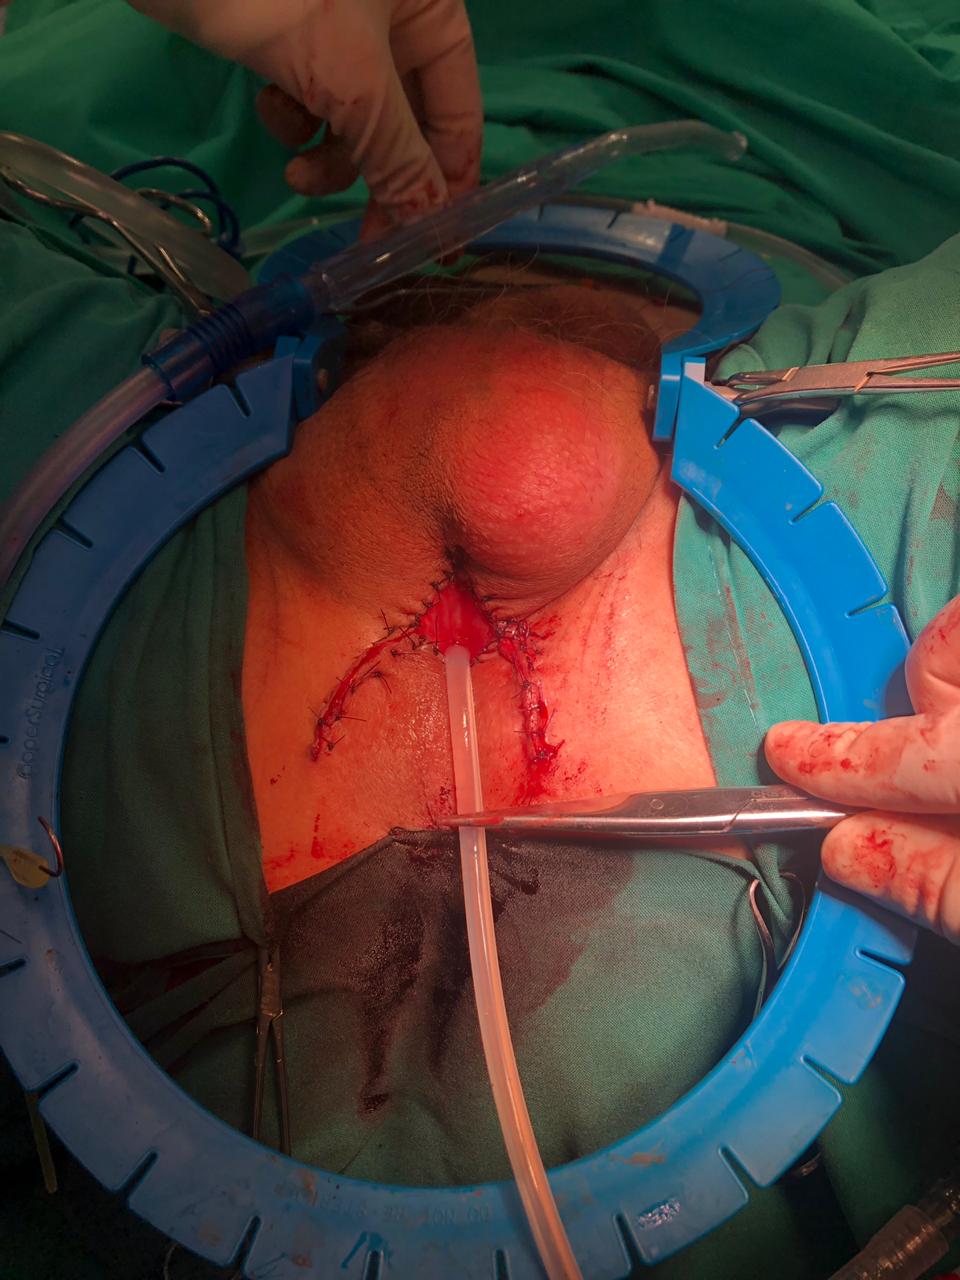

Se instala mediante una incisión perineal, con apertura del músculo bulboesponjoso y liberación circunferencial de la uretra bulbar (generalmente proximal o media), donde se instala el manguito. El balón regulador se instala en la región inguinal, en el espacio pre-peritoneal. La bomba se instala a través de esta última incisión, disecando en forma subcutánea hasta instalarla en el escroto. El dispositivo se activa a las 4-6 semanas.

- Excisión y reparación del ostium (Figura 23): Por abordaje vaginal, ya sea una incisión lineal sobre la lesión o en U invertida, se identifica y diseca el divertículo y su ostium. Se resecan las paredes del divertículo que se envía a anatomía patológica y se cierra el ostium con material reabsorbible delgado. Se recomienda un segundo plano no superpuesto de refuerzo a nivel de la fascia vaginal y luego el cierre de la vagina. En caso de requerir irrigación adicional, se recomienda el uso en este momento de un colgajo local como la grasa del labio mayor o flap de Martius.